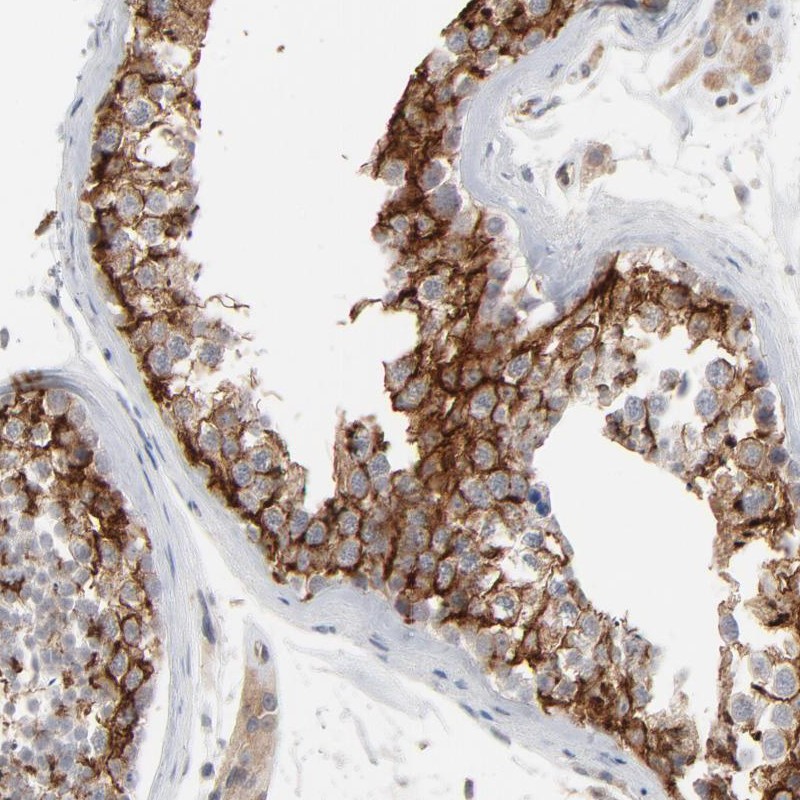

Immunohistochemical staining of human testis shows cytoplasmic positivity in cells in seminiferus ducts.